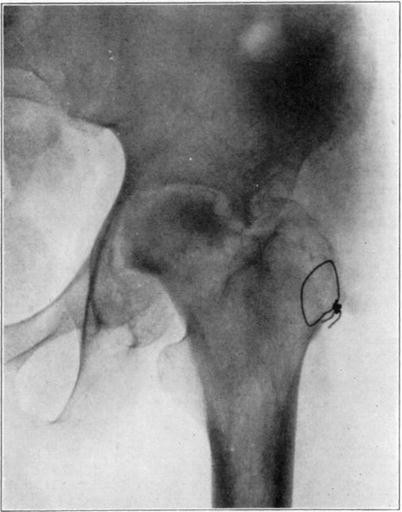

Case 3. Two hundred and seventy-four days after injury. Fracture of astragalus united. Superior and posterior part of body broken down and irregular while remaining portion dense and transformed. Indicative of necrosis of body with secondary changes.

Case 3. Eighteen months after injury, showing a defective but gradually reforming articular portion of the body of the astragalus.

The blood supply of the astragalus is derived mainly from a branch of the arteria dorsalis pedis which traverses the sinus tarsi lateral to the neck and breaks up to enter the bone near the junction of the neck and body along the lateral and inferior surfaces. There are very small branches entering the bone mesially and posteriorly at points of ligamentous and capsular attachments. Apparently when there is a fracture along the junction of body and neck the important vessels to the body are interrupted and there may be insufficient circulation through the remaining vessels, so that aseptic necrosis of a large part or all of the fragment follows. It is evident from the partial collapse which occurred in Case 3 that when necrosis of the body is diagnosed, the limb should be protected from weight-bearing for at least several months,—until union, revascularization, and transformation of necrotic area has been largely brought about. It seems probable that some of the bad results that have been reported in fracture of the neck of the astragalus, either united or ununited, have been due to overlooked aseptic necrosis of the body.